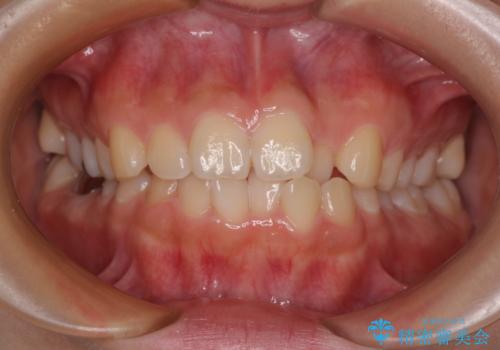

- 前歯のクロスバイトと口元の膨らんだ横顔の印象を気にして来院された患者様です。

レントゲン写真の分析結果からは、それほど口元が突出しているという結果にはなりませんでした。

しかしながら、唇を閉じたときに口元に緊張感があり、そのまま叢生を解消すると横顔が突出した印象になる可能性が高かったため、上下左右の小臼歯4本を抜歯して、ワイヤー装置にて矯正治療を行うこととしました。